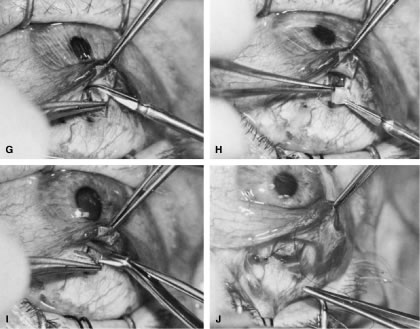

is paid to bringing it into view.   Fig. 14. Placement of a superior rectus muscle bridle suture. A. The eye with a Barraquer-Colibri speculum in place. The superior rectus

muscle is well hidden by the upper lid (lower portion of photograph). B. The needle of a single-armed 4-0 black silk suture is used to retract

the upper lid, allowing better visualization of the area in which the

superior rectus suture is to be placed. C. The tips of a Lister forceps are held tangential to the superior portion

of the globe, approximately 2 mm apart. D. The forceps are moved superiorly so that the tips extend past the insertion

of the superior rectus muscle, about 12 mm superior to the lumbus. E. Side view showing the lid held superiorly by the needle of the 4-0 black

silk suture and the Lister forceps in its initial position. F. The handle of the forceps is rotated superiorly while the tips are pressed

firmly against the globe. The indentation of the globe is caused

by the pressure of the forceps. When the forceps have been rotated to

the position shown, the tips are closed around the superior rectus muscle. G. After the muscle has been grasped firmly, the forceps are again rotated

inferiorly and the globe is pulled inferiorly. H. Surgeon's view of the proper grasp of the superior rectus muscle. I. The needle of the 4-0 black silk suture is placed under the superior rectus

muscle not through its belly. J. Proper position of the needle, deep to the forceps and between the globe

and the superior rectus muscle belly. (Spaeth GL. Glaucoma surgery. In Spaeth GL (ed). Ophthalmic Surgery: Principles

and Practice. Philadelphia: WB Saunders, 1990.) Fig. 14. Placement of a superior rectus muscle bridle suture. A. The eye with a Barraquer-Colibri speculum in place. The superior rectus

muscle is well hidden by the upper lid (lower portion of photograph). B. The needle of a single-armed 4-0 black silk suture is used to retract

the upper lid, allowing better visualization of the area in which the

superior rectus suture is to be placed. C. The tips of a Lister forceps are held tangential to the superior portion

of the globe, approximately 2 mm apart. D. The forceps are moved superiorly so that the tips extend past the insertion

of the superior rectus muscle, about 12 mm superior to the lumbus. E. Side view showing the lid held superiorly by the needle of the 4-0 black

silk suture and the Lister forceps in its initial position. F. The handle of the forceps is rotated superiorly while the tips are pressed

firmly against the globe. The indentation of the globe is caused

by the pressure of the forceps. When the forceps have been rotated to

the position shown, the tips are closed around the superior rectus muscle. G. After the muscle has been grasped firmly, the forceps are again rotated

inferiorly and the globe is pulled inferiorly. H. Surgeon's view of the proper grasp of the superior rectus muscle. I. The needle of the 4-0 black silk suture is placed under the superior rectus

muscle not through its belly. J. Proper position of the needle, deep to the forceps and between the globe

and the superior rectus muscle belly. (Spaeth GL. Glaucoma surgery. In Spaeth GL (ed). Ophthalmic Surgery: Principles

and Practice. Philadelphia: WB Saunders, 1990.)